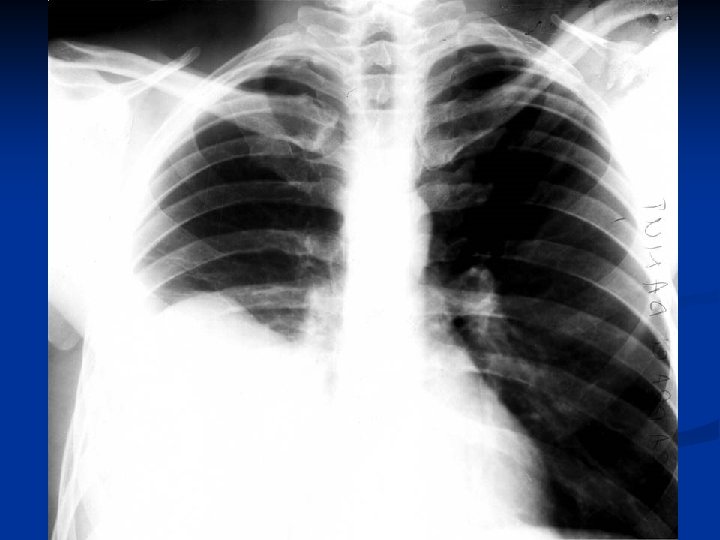

Caracteristici generale n n n Boala parazitara determinata de Taenia echinococcus granulosus. Descrisa inca de pe vremea lui Hipocrat si a lui Galen. Termenul de “chist hidatic” utilizat de Rudolphi in 1908. Localizarea pulmonara este a doua ca frecventa dupa cea hepatica. Boala cu distributie endemica in regiunea mediteraneana, Orientul Mijlociu, Australia, Noua Zeelanda, America de Sud.

Material si Metoda n Studiul de fata analizeaza retrospectiv 162 de cazuri operate in

Material si Metoda n Studiul de fata analizeaza retrospectiv 162 de cazuri operate in perioada 1999 – 2003.